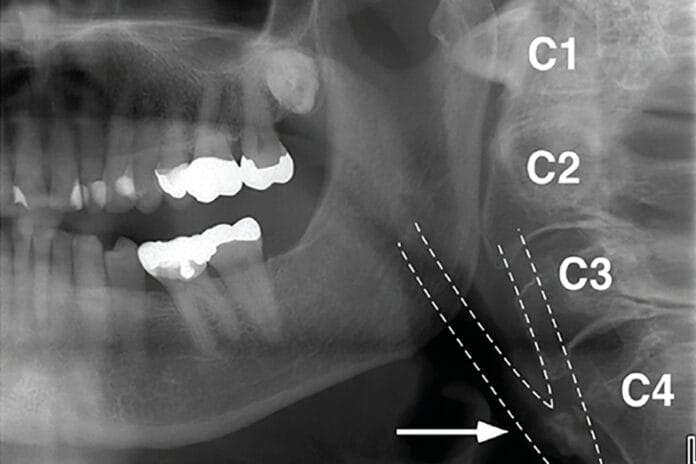

Panoramic and 3-Dimensional Images: Can They Detect Potential Carotid Artery Disease?

Panoramic (PAN) and three-dimensional radiographs such as cone beam computed tomography (CBCT) provides invaluable information for clinicians for various reasons. These types of imaging...